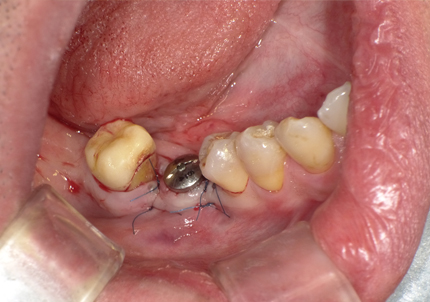

6.二次手術

インプラント周囲の角化歯肉(付着歯肉:骨に固定されてる歯肉)の獲得を目的に歯肉弁を移動する